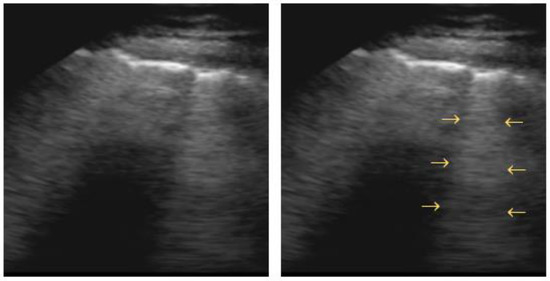

4.4. Pleural Effusion

- Treml, B.; Rajsic, S.; Diwo, F.; Hell, T.; Hochhold, C. Small Drainage Volumes of Pleural Effusions Are Associated with Complications in Critically Ill Patients: A Retrospective Analysis. J. Clin. Med. 2021, 10, 2453. [Google Scholar] [CrossRef]

- Yu, C.J.; Yang, P.C.; Chang, D.B.; Luh, K.T. Diagnostic and Therapeutic Use of Chest Sonography: Value in Critically Ill Patients. AJR Am. J. Roentgenol. 1992, 159, 695–701. [Google Scholar] [CrossRef]

- Lichtenstein, D.; Hulot, J.S.; Rabiller, A.; Tostivint, I.; Mezière, G. Feasibility and Safety of Ultrasound-Aided Thoracentesis in Mechanically Ventilated Patients. Intensive Care Med. 1999, 25, 955–958. [Google Scholar] [CrossRef]

- Balik, M.; Plasil, P.; Waldauf, P.; Pazout, J.; Fric, M.; Otahal, M.; Pachl, J. Ultrasound Estimation of Volume of Pleural Fluid in Mechanically Ventilated Patients. Intensive Care Med. 2006, 32, 318–321. [Google Scholar] [CrossRef] [PubMed]

- Vignon, P.; Chastagner, C.; Berkane, V.; Chardac, E.; François, B.; Normand, S.; Bonnivard, M.; Clavel, M.; Pichon, N.; Preux, P.M.; et al. Quantitative Assessment of Pleural Effusion in Critically Ill Patients by Means of Ultrasonography. Crit. Care Med. 2005, 33, 1757–1763. [Google Scholar] [CrossRef] [PubMed]

- Roch, A.; Bojan, M.; Michelet, P.; Romain, F.; Bregeon, F.; Papazian, L.; Auffray, J.P. Usefulness of Ultrasonography in Predicting Pleural Effusions > 500 ML in Patients Receiving Mechanical Ventilation. Chest 2005, 127, 224–232. [Google Scholar] [CrossRef] [PubMed]

- Hassan, M.; Rizk, R.; Essam, H.; Abouelnour, A. Validation of Equations for Pleural Effusion Volume Estimation by Ultrasonography. J. Ultrasound 2017, 20, 267–271. [Google Scholar] [CrossRef]

- Eibenberger, K.L.; Dock, W.I.; Ammann, M.E.; Dorffner, R.; Hörmann, M.F.; Grabenwöger, F. Quantification of Pleural Effusions: Sonography versus Radiography. Radiology 1994, 191, 681–684. [Google Scholar] [CrossRef]

- Lichtenstein, D.; Goldstein, I.; Mourgeon, E.; Cluzel, P.; Grenier, P.; Rouby, J.J. Comparative Diagnostic Performances of Auscultation, Chest Radiography, and Lung Ultrasonography in Acute Respiratory Distress Syndrome. Anesthesiology 2004, 100, 9–15. [Google Scholar] [CrossRef]

- Yang, P.C.; Luh, K.T.; Chang, D.B.; Wu, H.D.; Yu, C.J.; Kuo, S.H. Value of Sonography in Determining the Nature of Pleural Effusion: Analysis of 320 Cases. AJR Am. J. Roentgenol. 1992, 159, 29–33. [Google Scholar] [CrossRef]

- Tsai, T.H.; Yang, P.C. Ultrasound in the Diagnosis and Management of Pleural Disease. Curr. Opin. Pulm. Med. 2003, 9, 282–290. [Google Scholar] [CrossRef] [PubMed]